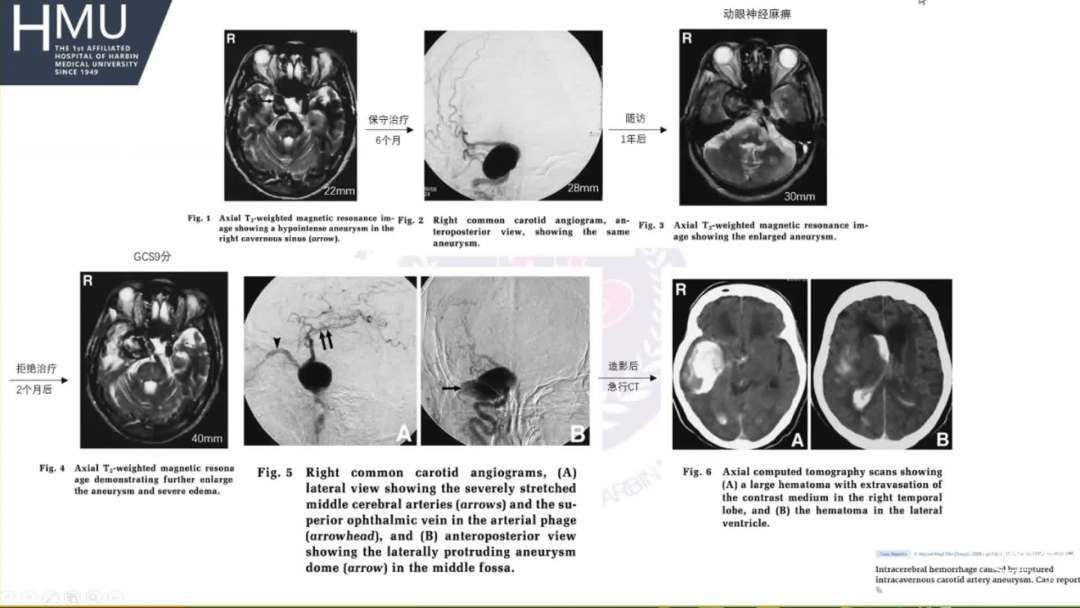

“SAH最有可能发生在动脉瘤扩张累及海绵窦硬膜”。

海绵窦段动脉瘤如何导致蛛网膜下腔出血?

破裂致下腔出血可能因素

●大动脉瘤累及突破海绵窦硬膜

●颅底内外环发育不全或松动

●海绵窦外侧壁先天薄弱区域

●大泌乳素瘤破坏海绵窦硬膜及骨质

●外伤所致假性动脉瘤合并骨折

●动脉瘤在随访期间进行性增大

●动脉瘤体大于20mm

●合并颅神经功能障碍

●合并巨大泌乳素瘤,应优先处理颅内动脉瘤